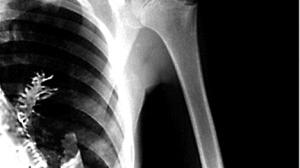

看病:“家门口”治疗一样行

“人工听骨链重建、心脏起搏器植入术、冠状动脉造影、单孔胸腔镜左肺动脉主干预阻断术等 , 一些高难度的、以前无法胜任的手术 , 龙游县人民医院现在都可以做了 , 这能够直接让百姓受益 。 ”周卫锦自豪地说 。

目前 , 邵医与龙游县人民医院合作学科12个 , 重点托管专科4个(耳鼻喉科、泌尿外科、胸外科、心血管内科) , 每批次派驻专家12名 , 共计派驻专家105人 , 成立邵医专家工作站17个 , 围绕“提能力、补短板、强特色”的基本原则和“一年出成果、两年大变样、五年新飞跃”的总体要求 , 助力龙游县人民医院跨越式高质量发展 。

“在龙游县人民医院 , 我们成立‘快速反应小组’ , 对外科进行专业化、精细化的划分 , 设置‘潜力医生培养项目’ , 督促医护人员自我提升 , 不断将邵医的理念融入医院 , 提升医院业务能力、管理水平 。 目前 , 龙游县县域病理中心建设也在稳步推进中 。 ”邵医派驻龙游县人民医院常务副院长张雷说 , “随着基层医院水平的提升 , 越来越多的患者选择了留在‘家门口’治疗 , 这节省了他们奔波的时间和费用 , 让患者切实享受到了省级的优质医疗服务 。 ”